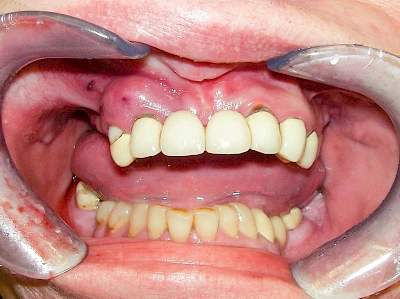

Ist zunächst nur das Zahnfleisch von der Entzündung betroffen, spricht man von Gingivitis. Später, wenn auch der Knochen um die Zähne herum entzündet ist, spricht man von einer Parodontitis. Bei der Parodontitis wird der Knochen nach und nach abgebaut und das Zahnfleisch zieht sich zurück. Die Zahnhälse und Zahnwurzeloberflächen liegen mehr und mehr frei. Die Zähne werden zunehmend lockerer und fallen schließlich aus.